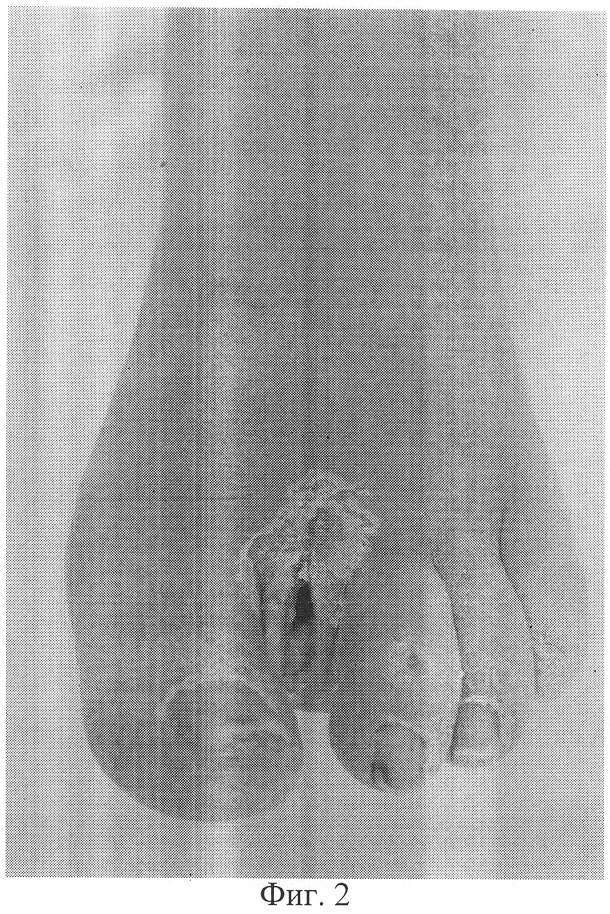

фиг.2 – фото конечности больного Н. до лечения;

Больной Н. (фиг.1, 2) поступил в клинику с диагнозом: Сахарный диабет, II тип, субкомпенсация. Синдром диабетической стопы слева. Трофическая язва в области ампутированного II пальца левой стопы. Диабетическая ангиопатия. Перемежающаяся хромота через 150-200 метров. На артериограмме прослеживается локальная (4-5 см) окклюзия поверхностной бедренной артерии в средней трети, многочисленные стенотические поражения магистральных артерий на протяжении голени и стопы.